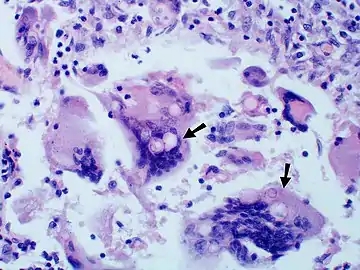

Large, broadly-based budding yeast cells characteristic of Blastomyces dermatitidis in a GMS-stained biopsy section from a human leg.

Inhaled conidia of Blastomyces are phagocytosed by neutrophils and macrophages in alveoli. Some of these escape phagocytosis and transform into yeast phase rapidly. Having thick walls, these are resistant to phagocytosis. Once they have transitioned to the yeast phase, the Blastomyces cells express the protein BAD-1, which helps the yeast cells attach to host cells, and also impairs activation of immune cells while inhibiting release of tumor necrosis factor. [23] In lung tissue, the cells multiply and may also disseminate through blood and lymphatics to other organs, including the skin, bone, genitourinary tract, and brain. The incubation period for pulmonary blastomycosis is 3 to 15 weeks, although 3050% of infections are asymptomatic.[24]

Once suspected, the diagnosis of blastomycosis can usually be confirmed by demonstration of the characteristic broad based budding organisms in sputum or tissues by KOH prep, cytology, or histology.[27] Tissue biopsy of skin or other organs may be required in order to diagnose extra-pulmonary disease. Blastomycosis is histologically associated with granulomatous nodules.